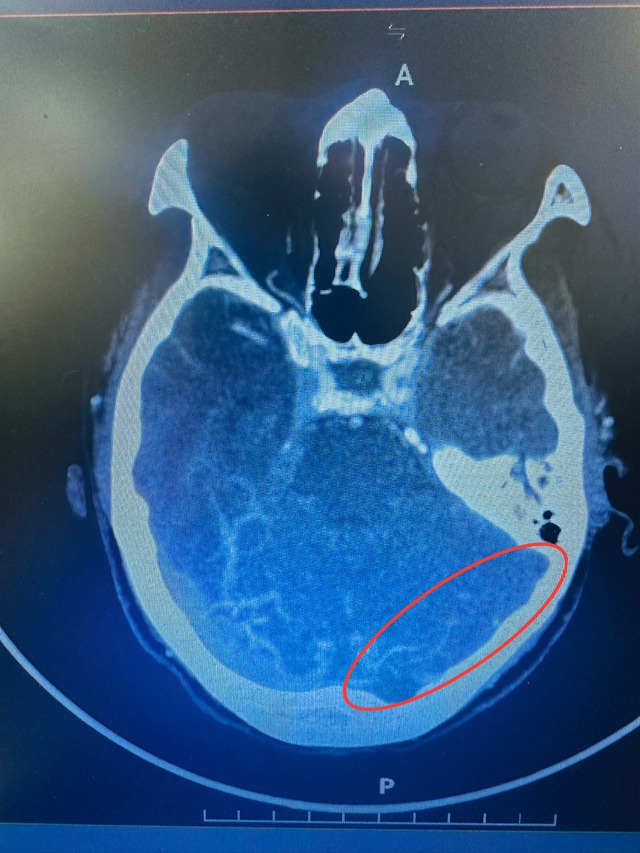

Kết quả chụp cắt lớp vi tính sọ não xác định BN bị chảy máu não lớn chuyển dạng thùy đỉnh 2 bên do huyết khối xoang tĩnh mạch dọc trên và hội lưu xoang. Xét nghiệm D-Dimer (đánh giá tình trạng khối máu đông trong mạch máu) tăng cao trên 5.000 ng/mL. Sau đợt điều trị tích cực, BN đã tỉnh, cai được máy thở, giao tiếp được và sinh hoạt chủ động một phần.

Trường hợp khác là nữ BN trẻ tuổi vào viện do đau đầu kéo dài, yếu nửa người trái tăng dần, khó đi lại. Qua kết quả chụp và các xét nghiệm, các bác sĩ chẩn đoán BN nhồi máu não vùng thái dương phải do huyết khối xoang thẳng, xoang sigma và xoang ngang trái. BN được điều trị nội khoa bằng thuốc chống đông theo phác đồ và đã hồi phục tốt, ra viện với khả năng sinh hoạt độc lập.

Phim chụp chẩn đoán cho thấy hình ảnh chảy máu não lớn ở bệnh nhân nữ bị đột quỵ

ẢNH: NGỌC AN